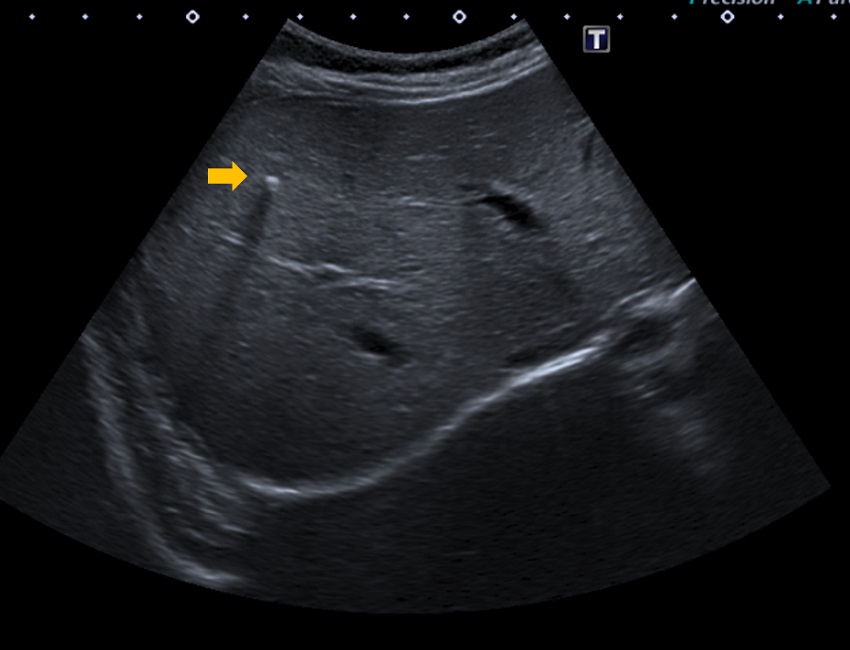

Lactante de sexo masculino normoconfigurado de un mes y 21 días, sin antecedentes familiares de interés, remitido a consultas de Digestivo desde la consulta de Neonatología para estudio y seguimiento de calcificaciones hepáticas advertidas durante el seguimiento gestacional, en el segundo trimestre de embarazo. Embarazo controlado. Rotura de bolsa tras amniocentesis en la semana 15, con recuperación posterior de líquido amniótico. Crecimiento intrauterino retardado, estadio I. Parto por cesárea en la semana 37, peso de recién nacido de 2400 gramos. Apgar 8/9; reanimación 1. Taquipnea transitoria del recién nacido leve. Serologías de rubeola inmune, resto negativo. Cribado endocrinometabólico negativo. Se solicita ecografía abdominal, en la que se observan múltiples calcificaciones perihepáticas en ambos lóbulos hepáticos, con algún foco intrahepático, sin signos de peritonitis meconial (Fig. 1).

| Figura 1. Imágenes hiperecogénicas subcapsulares hepáticas, con sombras posteriores, compatibles con calcificaciones hepáticas |